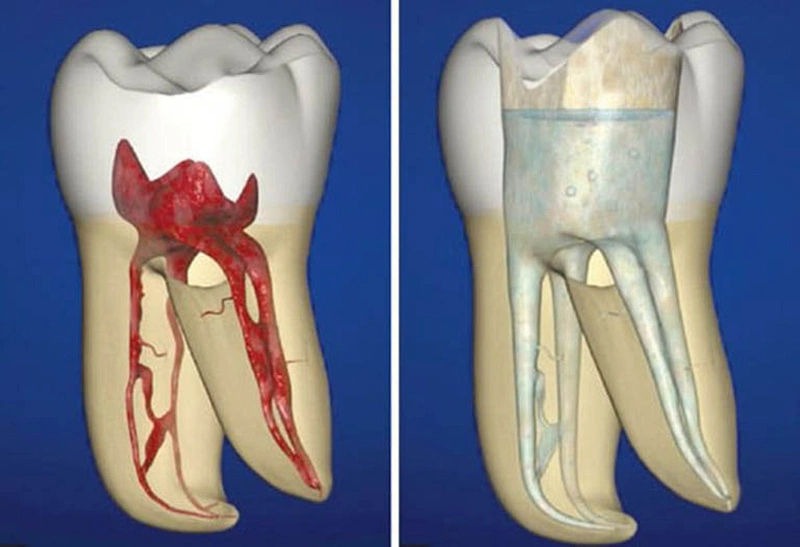

Tủy răng là một trong những bộ phận quan trọng trong cấu trúc của răng. Bộ phận này có nhiều mạch máu giúp nuôi dưỡng và dẫn

Hiện nay, việc lấy tủy khi thực hiện phục hình răng miệng đang trở nên phổ biến. Việc này nhằm khắc phục vấn đề hư hỏng ở